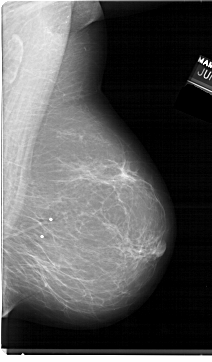

ics_version 1.0 filename A-1398-1 DATE_OF_STUDY 19 6 1992 PATIENT_AGE 62 FILM FILM_TYPE REGULAR DENSITY 2 DATE_DIGITIZED 9 9 1998 DIGITIZER HOWTEK 43.5 SEQUENCE LEFT_CC LINES 6526 PIXELS_PER_LINE 4201 BITS_PER_PIXEL 12 RESOLUTION 43.5 OVERLAY LEFT_MLO LINES 6871 PIXELS_PER_LINE 4186 BITS_PER_PIXEL 12 RESOLUTION 43.5 OVERLAY RIGHT_CC LINES 6466 PIXELS_PER_LINE 3826 BITS_PER_PIXEL 12 RESOLUTION 43.5 NON_OVERLAY RIGHT_MLO LINES 6871 PIXELS_PER_LINE 4021 BITS_PER_PIXEL 12 RESOLUTION 43.5 NON_OVERLAY |